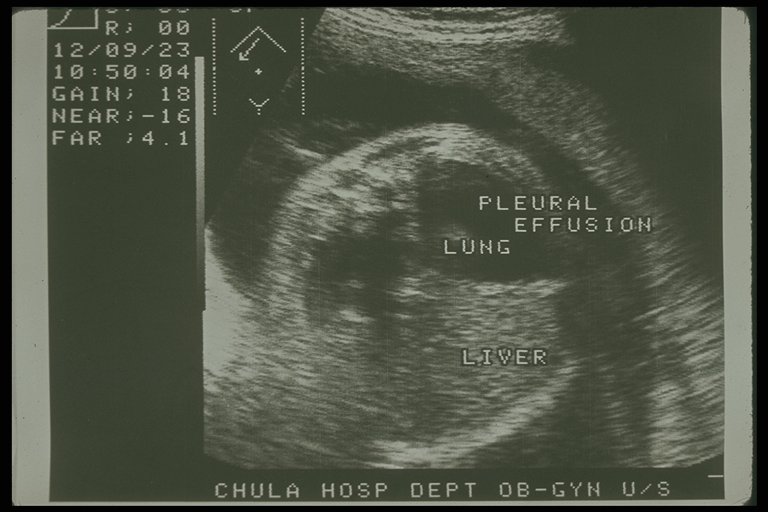

Prenatal ultrasonography showed bilateral congenital chylothorax, massive pleural effusion was detected in both chest cavity